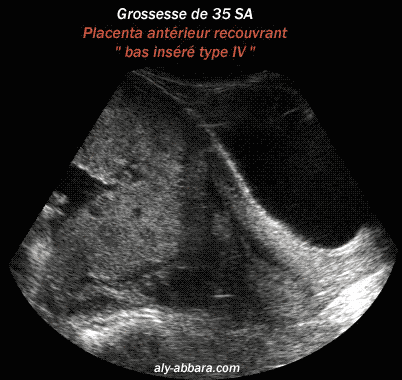

Placenta prævia, antérieur recouvrant

(Type IV selon BESSIS R, BRIGNON C, SCHNEIDER

L. 1976)

à 35 semaines d'aménorrhée

Cette image montre l'insertion anormale

du placenta ; il s'insère sur la paroi antérieure du segment

inférieur,

et recouvre l'orifice interne du col utérin et la paroi postérieure

du segment inférieur